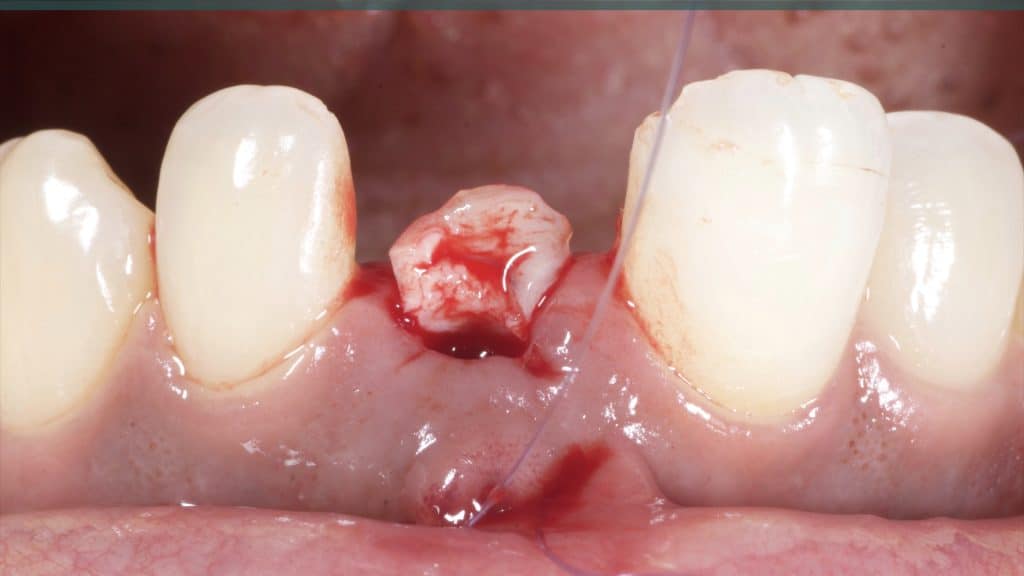

A 27-year female patient with dislodged Resin bonded FPD. She had that FPD for past few years, it had metal wings on palatal surfaces of UR1 and UL2 and a post like metal extension into the root canal of UL1. There was gingival abscess due to fractured root segment most probably due to extended metallic post like structure. Immediate implant placement (IIP) and Immediate restoration (IR) was planned for this patient.

Immediate post-op